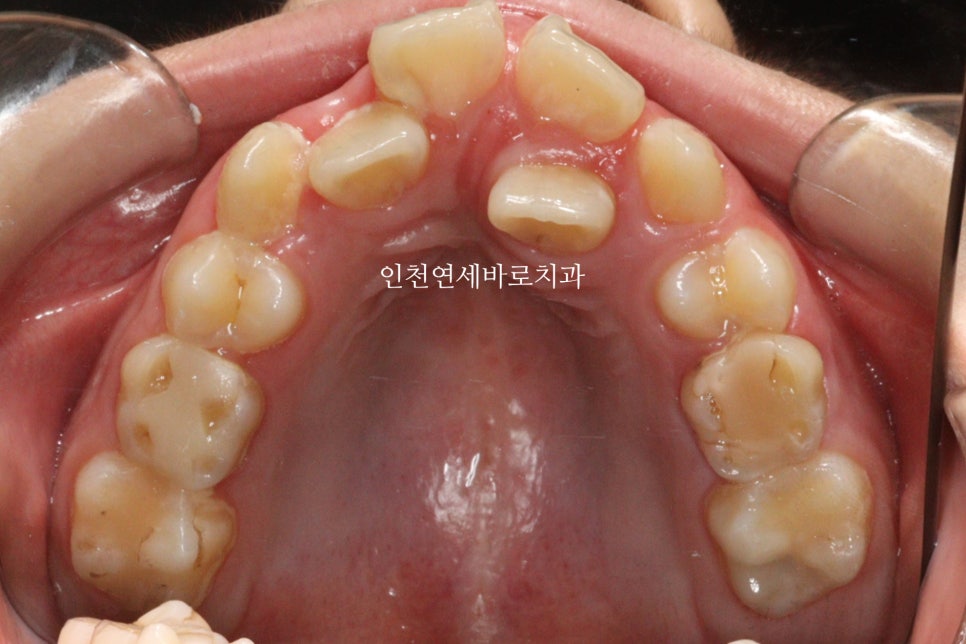

심한 덧니를 가진 아이가 병원에 왔습니다.

비발치 치료계획을 세운뒤 #인비절라인퍼스트 주문을 했습니다.

약한달이 지나고 치료를 처음 시작한 날의 모습입니다.